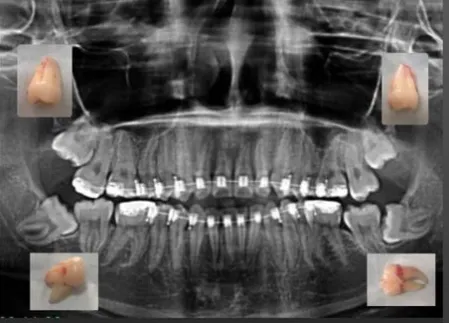

Vemos exactamente dónde están raíces, nervios y posición real.

Confirmamos si realmente necesitas la extracción y qué tan compleja será.

Radiografía panorámica.

Plan de tratamiento para tus muelas del juicio.